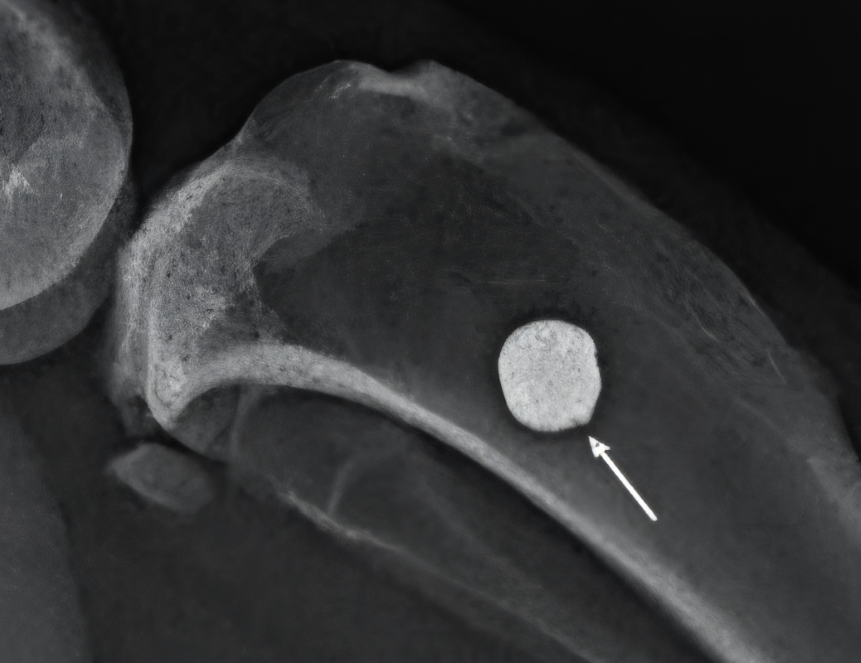

Ученые из Института металлургии и материаловедения имени А.А. Байкова РАН (Москва) и Национального медицинского исследовательского центра травматологии и ортопедии имени академика Г.А. Илизарова (Курган) обнаружили, что не все часто используемые в имплантатах редкоземельные металлы и их примеси безопасны для живых существ. Авторы провели исследование на 46 самцах крыс, которых разделили на четыре группы. Первой под кожу ввели титановый имплантат с добавлением иттрия, второй — с лантаном, третьей — с церием, а четвертой (контрольной) поместили чистый титановый имплантат. В течение следующих четырех недель исследователи оценивали общее состояние здоровья животных, массу, температуру их тела и локальную температуру в месте установки имплантата.